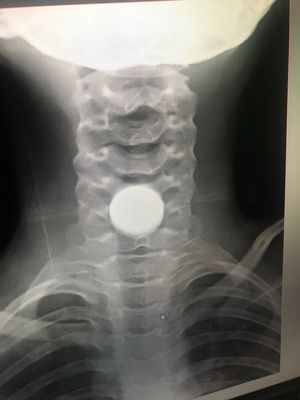

Coin in esophagus

10 year Child swollen coin and obstructing esophagus